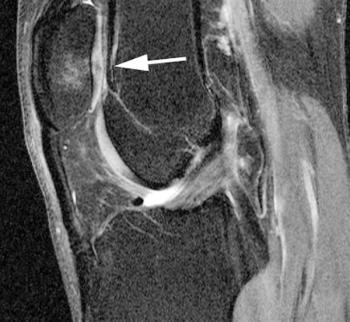

Using 3T MR imaging, California researchers have found that high levels of physical activity may be linked to knee abnormalities in middle-aged men and women. People between the ages of 45 and 55 who engage in several hours of walking, sports, or other types of exercise per week may be at greater risk of developing osteoarthritis than less active adults, according to a study presented Monday at the 2009 RSNA meeting.